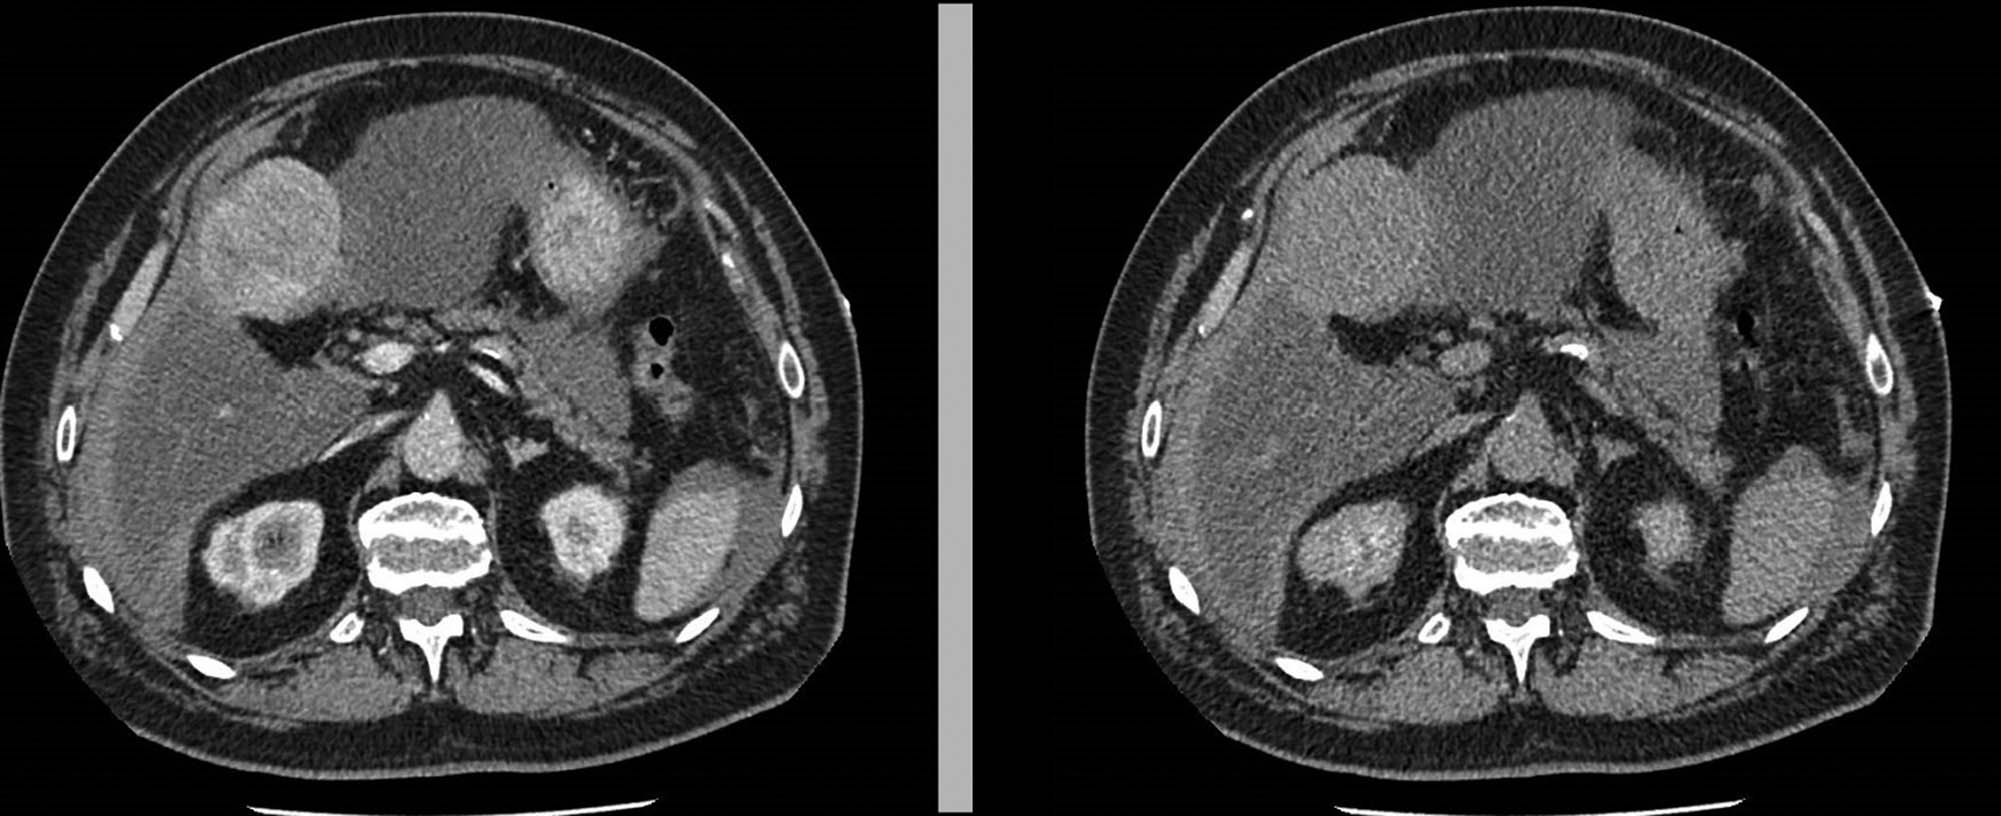

An urgent ultrasonographic examination was performed, which showed fluid in the peritoneal cavity and an unidentified hepatic neoformation without other relevant findings. After administration of fluids and two units of leukodeplete blood cells, the vital parameters normalized and the patient was stabilized. A chest abdomen CT with contrast was required (Figure 1).

Neoformation of the IV hepatic segment.

The TC images showed an oval neoformation with clear margins endowed with inhomogeneous enhancement, partly exophytic, at the level of the IV hepatic segment, with dimensions of 67 × 56 × 58 mm. The finding was not of unequivocal interpretation, therefore it had to be correlated to the biohumoral and clinical panel. Perihepatic and perisplenic blood effusion was also reported, but in the absence of active contrast spills. The liver appeared as enlarged as for chronic but not cirrhotic epatopathy, with the caliber of the inferior vena cava reduced. There are no other noteworthy findings.